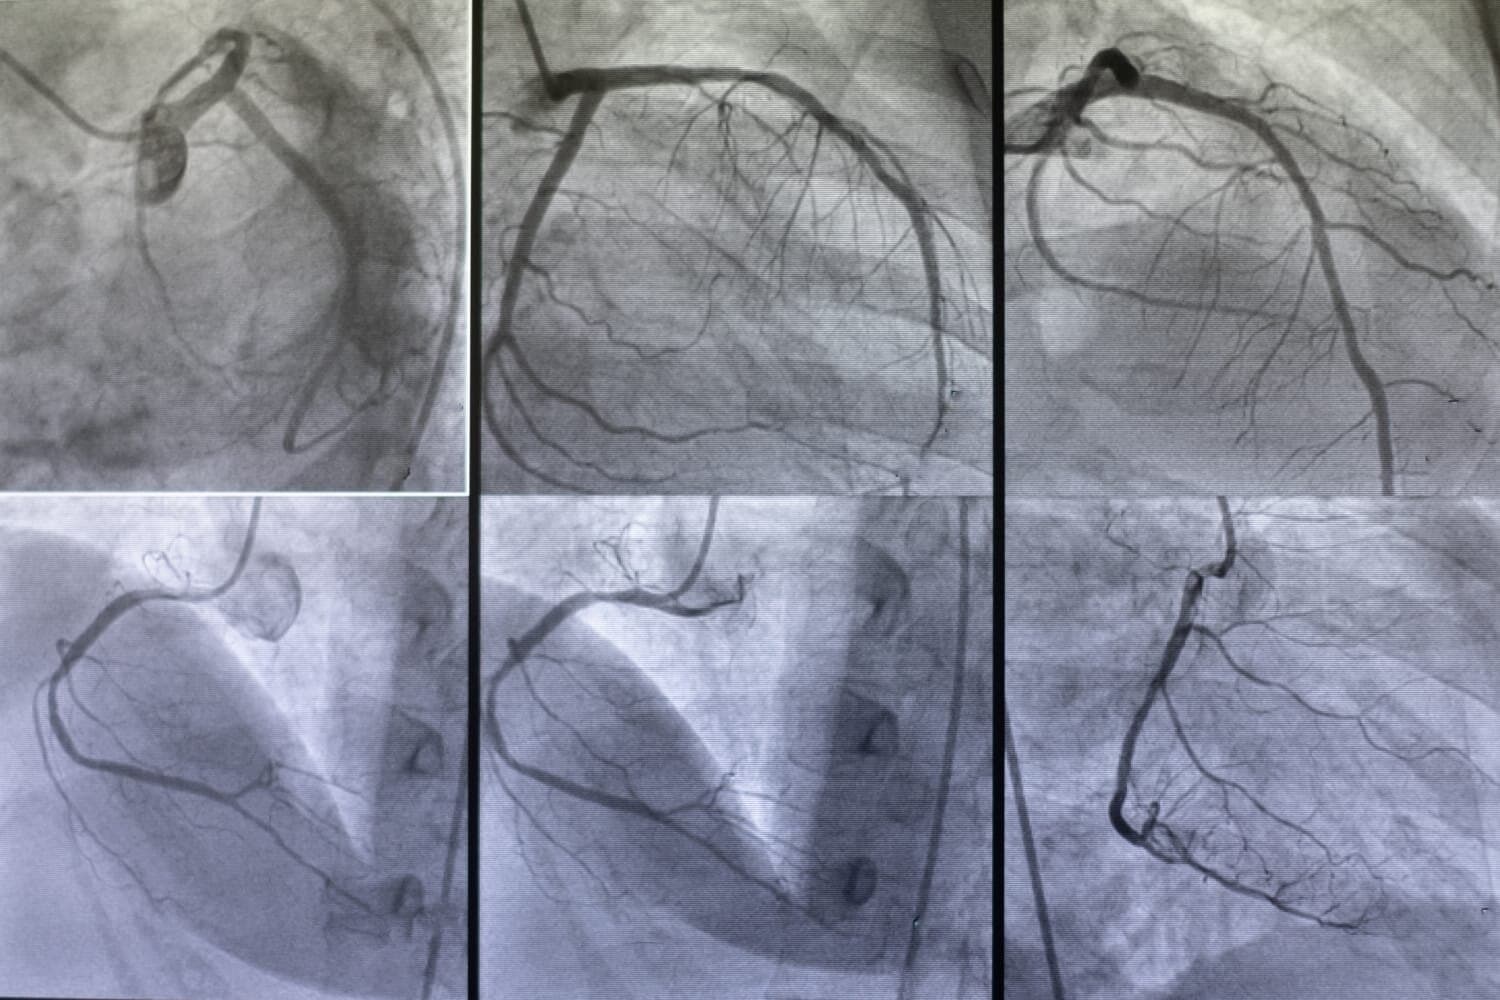

There are different types of angiographies, each tailored to specific diagnostic needs. Coronary angiography, for instance, is used to examine the arteries supplying blood to the heart, helping to diagnose coronary artery disease and guide interventions such as angioplasty or stenting. Cerebral angiography focuses on the blood vessels in the brain, aiding in the detection of aneurysms, arteriovenous malformations, or blockages that could lead to stroke. Pulmonary angiography examines the blood vessels in the lungs, often used to diagnose conditions like pulmonary embolism.

Angiography is a crucial diagnostic tool used to assess blood vessels and identify various cardiovascular conditions, making it essential for a wide range of patients. Individuals who exhibit symptoms of heart disease, such as chest pain (angina), shortness of breath, dizziness, or unexplained fatigue, are prime candidates for angiography. These symptoms can indicate the presence of blockages or narrowing in the coronary arteries, which can lead to serious conditions like heart attacks if left untreated. Angiography helps doctors visualize these blockages and plan appropriate interventions.

Patients with a history of heart disease or those who have undergone previous cardiac procedures, such as angioplasty or coronary artery bypass grafting (CABG), may also require angiography. This procedure can monitor the effectiveness of prior treatments and detect any new or recurring issues in the blood vessels. Additionally, individuals with congenital heart defects or structural abnormalities of the heart and blood vessels may need angiography for accurate diagnosis and surgical planning.